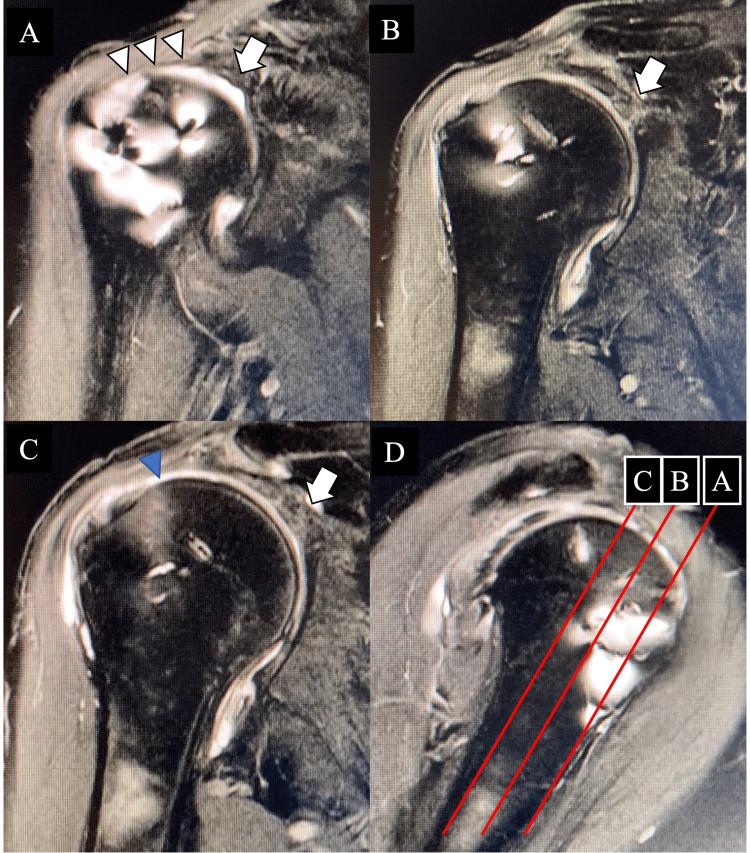

同种异体移植重建上盂唇和肩袖撕裂后同一患者肩部肩峰下滑囊炎的比较:病例报告

This paper reports a pathological comparison between the synovium of the shoulder with rotator cuff tears (RCTs) with or without an allograft in the same patient and assesses allograft remodeling after superior capsular reconstruction (SCR). A 49-year-old man underwent SCR with a fascia lata allograft for irreparable RCTs. Two years postoperatively, the patient underwent arthroscopic rotator cuff repair for left RCTs and arthroscopic debridement to alleviate right shoulder pain. Additionally, revascularization was confirmed in the allograft of the fascia lata. In conclusion, allografts are considered highly safe and expected to be engrafted after SCR.

本文报告了同一患者有或没有同种异体移植的肩袖撕裂(RCT)的肩关节滑膜之间的病理学比较,并评估了上盂唇重建(SCR)后同种异体移植的重塑情况。一名49岁男性因不可修复的RCT接受了阔筋膜同种异体移植的SCR。术后两年,该患者接受了关节镜下肩袖修复治疗左侧RCT,并进行了关节镜下清创术以缓解右肩疼痛。此外,阔筋膜同种异体移植中证实有血管再生。总之,同种异体移植被认为是高度安全的,并且有望在SCR后植入。